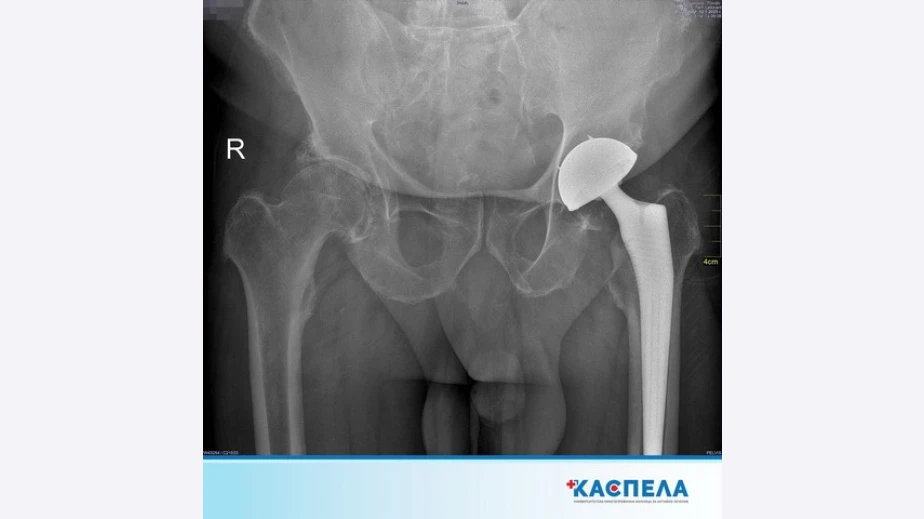

Диагностицирането на коксартрозата се извършва чрез клиничен преглед и образни изследвания, като рентгенографията е основният метод за оценка на състоянието на ставата. В ранните стадии лечението включва консервативни методи като физиотерапия, медикаментозна терапия и промени в начина на живот с цел забавяне на прогресията на заболяването. Въпреки това, когато болката стане постоянна и двигателната активност се влоши значително, единственото ефективно решение остава оперативното лечение.

„Ендопротезирането, или смяната на тазобедрената става, е стандартна и високоефективна процедура, която значително подобрява качеството на живот на пациентите. Чрез операцията увредената става се заменя с изкуствена, което напълно елиминира болката и възстановява мобилността. Днес благодарение на съвременните импланти и минимално инвазивните техники пациентите могат да се върнат към активния си начин на живот в рамките на няколко месеца", споделя д-р Благой Постоловски, ортопед в УМБАЛ Каспела.